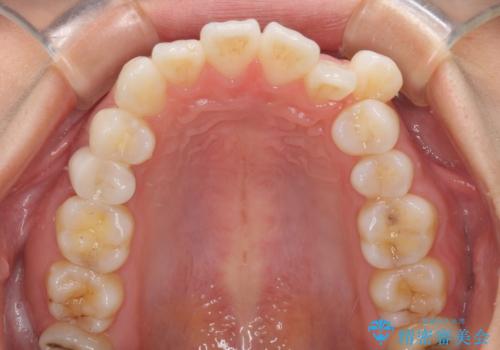

- 八重歯と口元の突出感を気にして来院された患者様です。

歯列が前方に突出しており、上下の正中がズレていたため、左側は上下第一小臼歯を、右側は上下第二小臼歯を抜去し、ワイヤー装置による矯正治療を行うこととしました。

当初はインビザラインによる矯正治療をご希望でしたが、正中を合わせたいことや、口元の突出感を改善したいことから、ワイヤー矯正を強く推奨しました。

治療期間は2年に満たず、スッキリとした口元に仕上がりました。